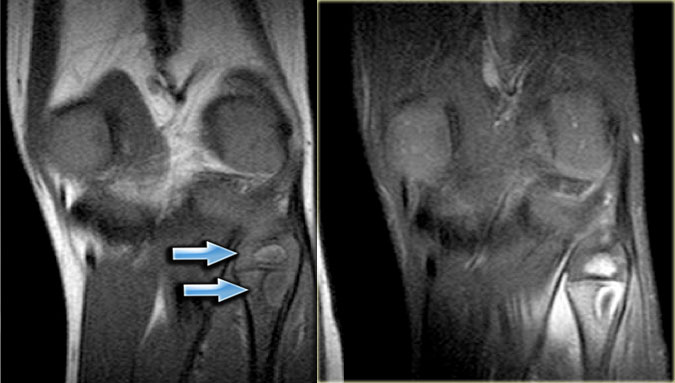

Here images of a 30-year-old male.

There is a wel-defined lytic lesion of the olecranon with several ridges and a pathologic fracture.

The differential diagnosis includes giant cell tumor and ABC.

The T2WI+FS shows fluid-levels due to sedimentation making ABC the most likely diagnosis.

Biopsy however revealed Brown tumor.